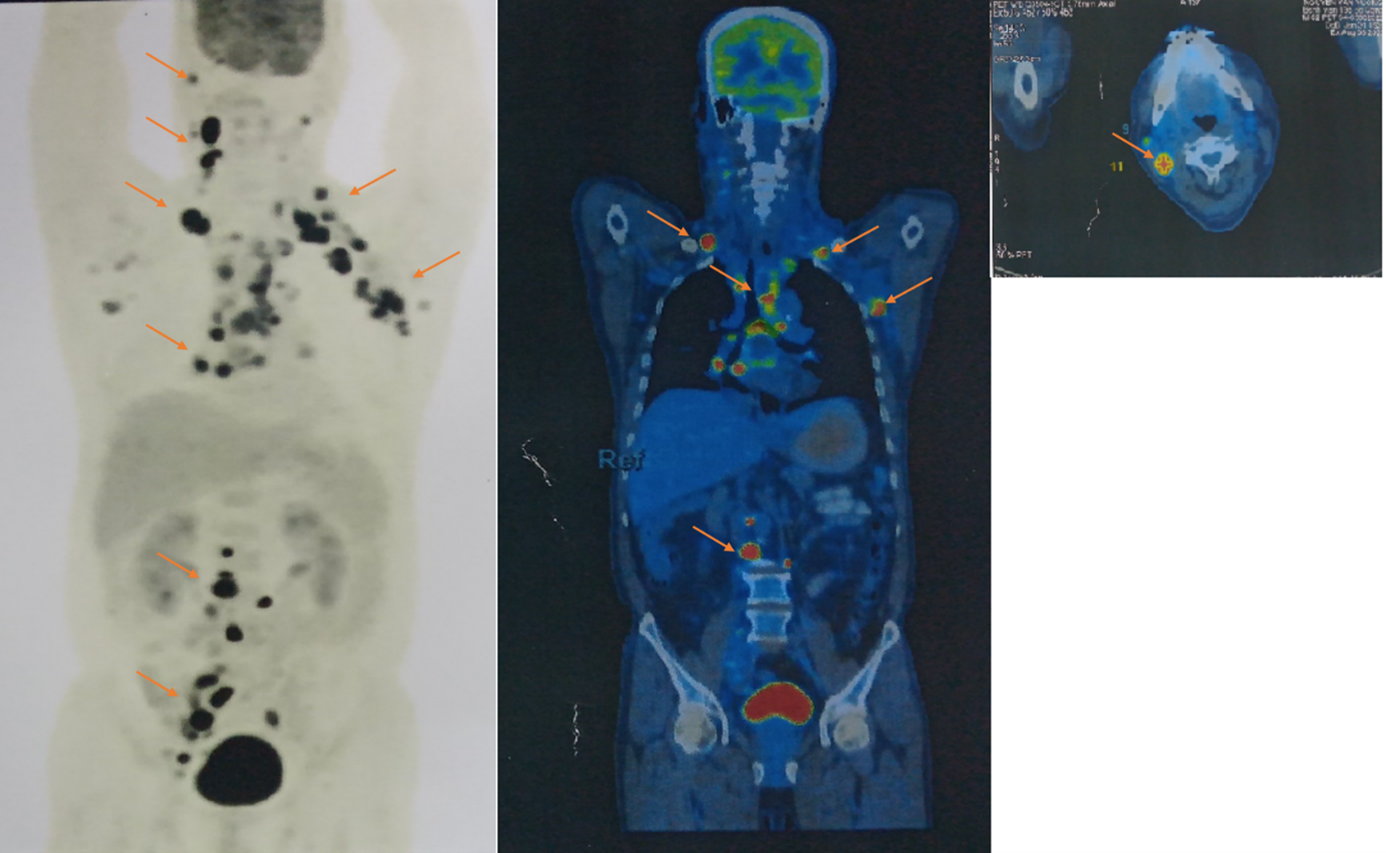

- PET/CT: các hạch lớn vùng cổ, nách, trung thất, ổ bụng gần như mất hoàn toàn hoặc giảm kích thước đáng kể, không còn vị trí tăng chuyển hoá FDG bất thường.

Hình 5: Không thấy vị trí tăng chuyển hoá FDG bất thường trên phim PET/CT sau điều trị

Hình 6: Không còn thấy tổn thương phổi

Kết luận:

- Hình ảnh hạch nách 2 bên, lớn nhất 7mm, hạch chậu phải 11mm, đều không tăng chuyển hoá FDG.

- Chưa phát hiện hình ảnh tổn thương tăng chuyển hoá FDG khú trú, bất thường ở vị trí khác trên PET/CT toàn thân.

 Như vậy bệnh đáp ứng hoàn toàn trên phim PET/CT.